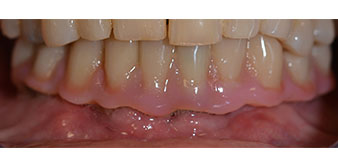

L'empreinte et l'enregistrement de l'occlusion ont ensuite été effectués afin que le prothésiste dentaire puisse commencer à réaliser la restauration provisoire. Celle-ci a été vissée le jour même (Fig. 17 et 18).

Implants

Fig. 17

Fig. 18

Après ostéointégration, l'empreinte finale des implants a été effectuée et la prothèse finale a été fabriquée en conséquence (Fig. 19 et 20). À cette étape, le praticien et le patient ont pu décider ensemble d'utiliser une facette dentaire en céramique ou en acrylique et une armature en zircone ou en métal. Dans ce cas, l'équipe du Dr Pascu a opté pour une facette dentaire en acrylique en raison du pronostic incertain de la denture maxillaire et du fait que la dent 24 est extrusée. Ce type de facette est plus facile à ajuster et peut donc être modifiée selon la nouvelle situation maxillaire.

Ostéointégration

Fig. 19

Fig. 20